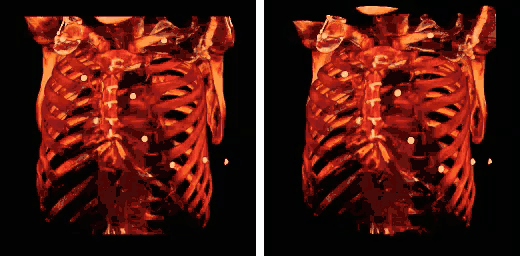

Note also that the colour look-up table (CLUT) can be varied to highlight features of particular interest, as shown in the set of images below:

The influence of the opacity table is illustrated in the following example images:

The influence on volume rendering of various shading settings is shown below:

The shading settings used for the above images are as follows:

| Image | Ambient Coefficient | Diffuse Coefficient | Specular Coefficient | Specular Power |

|---|---|---|---|---|

| Top Left | 0.15

|

0.9

0.3

15.0

| Top Middle | 0.75

| Top Right | 0.15

0.1

| Bottom Left | 0.15

1.2

| Bottom Middle | 0.15

1.0

| Bottom Right | 0.15

0.6